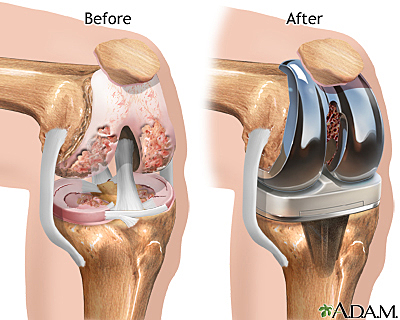

• Inspiration of the Development of Knee Replacements

Inspiration of the Development of Knee Replacements

In the early 1960s Sir John Charnley inspired development of the Condylar knee replacement.

• First Total Knee Replacement

First Total Knee Replacement

Dr. Gunston who worked with Sir John Charnley went on to implant the first polycentric knee with an unhinged knee design which replaced both the medial and lateral sides, therefore making it the first total knee replacement. This implant was designed to be a game changer for patients with arthritis where other medicine approaches such as physio therapy had failed. The implant recreated how real knees worked and was the first one to contain all the correct anatomically shaped parts in the knee.